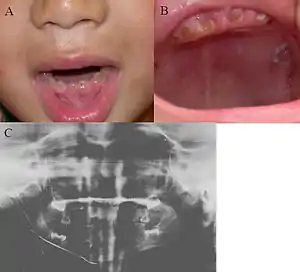

| Oral photographs from an individual with Dentinogenesis imperfecta | |

This condition can cause teeth to be discolored (most often a blue-gray or yellow-brown color) and translucent, giving teeth an opalescent sheen.[2][3][8][5][9] Teeth are also weaker than normal, making them prone to rapid wear, breakage, and loss.[2][3][4][5][8] These problems can affect baby (primary/deciduous) teeth alone, or both baby teeth and adult (permanent) teeth, with the baby teeth usually more severely affected.[5][8]

- Discoloured teeth - teeth may be amber, brown, blue or opalescent

- Bulbous shape to the tooth crown due to cervical constriction

- Tooth wear/Non-carious tooth surface loss (NCTSL) - due to the poorly mineralised dentine, the enamel of the tooth is unsupported and subsequently shears or chips off as it is subjected to biting forces. This exposes the underlying poorly mineralised dentine which is less resistant to wear. Therefore, features of abrasion and attrition may become apparent.

The baby (primary) teeth are usually more severely affected than adult (permanent) teeth.[3][5][8]